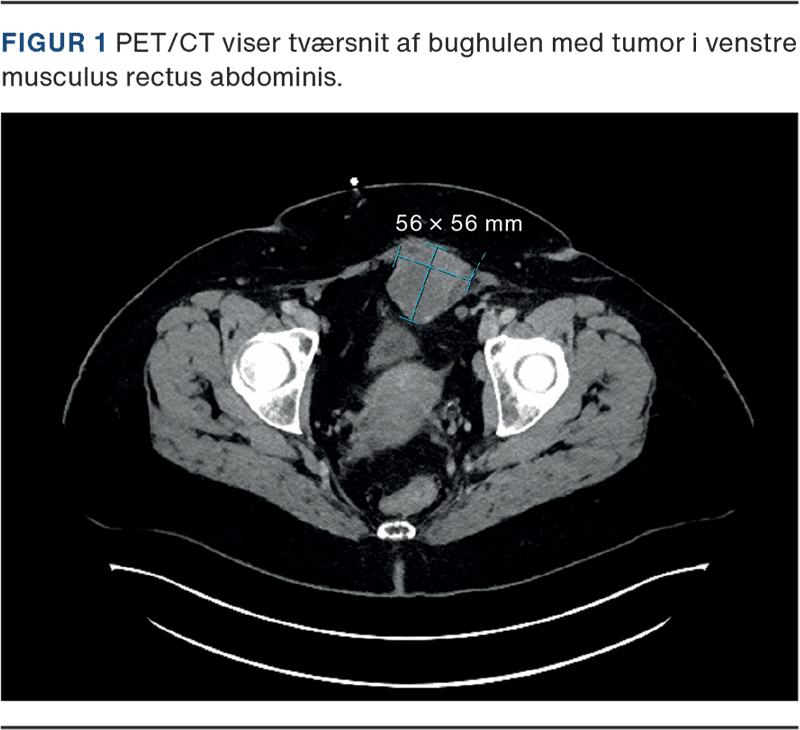

Patienten var symptomfri gennem en længere årrække, men efter seponering af hormonspiralen i 2023 udviklede hun igen en øm udfyldning i venstre fossa. Dette ledte til, at hun i oktober 2024, i en alder af 60 år, blev udredt i kræftpakkeforløb på mistanke om kolorektalcancer. Koloskopi viste kun benigne polypper, men en efterfølgende CT, udført på mistanke om ventralhernie, påviste en bløddelsproces i venstre rectus abdominis muskulatur (Figur 1). Der blev foretaget en MR-skanning for at udelukke sarkom. Skanningen gav imidlertid mistanke om recidiv af endometriose i sectiocikatricen, og patientens udredning i pakkeforløb blev derfor afsluttet. Patienten blev henvist til gynækologisk afdeling på Rigshospitalet, hvor en UL-vejledt biopsi viste clearcelle adenokarcinom.